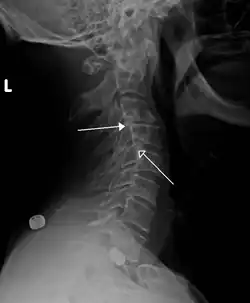

A hangman's fracture is a specific type of spondylolisthesis where the second cervical vertebra (C2) is displaced anteriorly relative to the C3 vertebra due to fractures of the C2 vertebra's pedicles.

Retrolisthesis

A retrolisthesis is a posterior displacement of one vertebral body with respect to the subjacent vertebra to a degree less than a luxation (dislocation). Retrolistheses are most easily diagnosed on lateral x-ray views of the spine. Views, where care has been taken to expose for a true lateral view without any rotation, offer the best diagnostic quality.

Retrolistheses are found most prominently in the cervical and lumbar region, but can also be seen in the thoracic area.